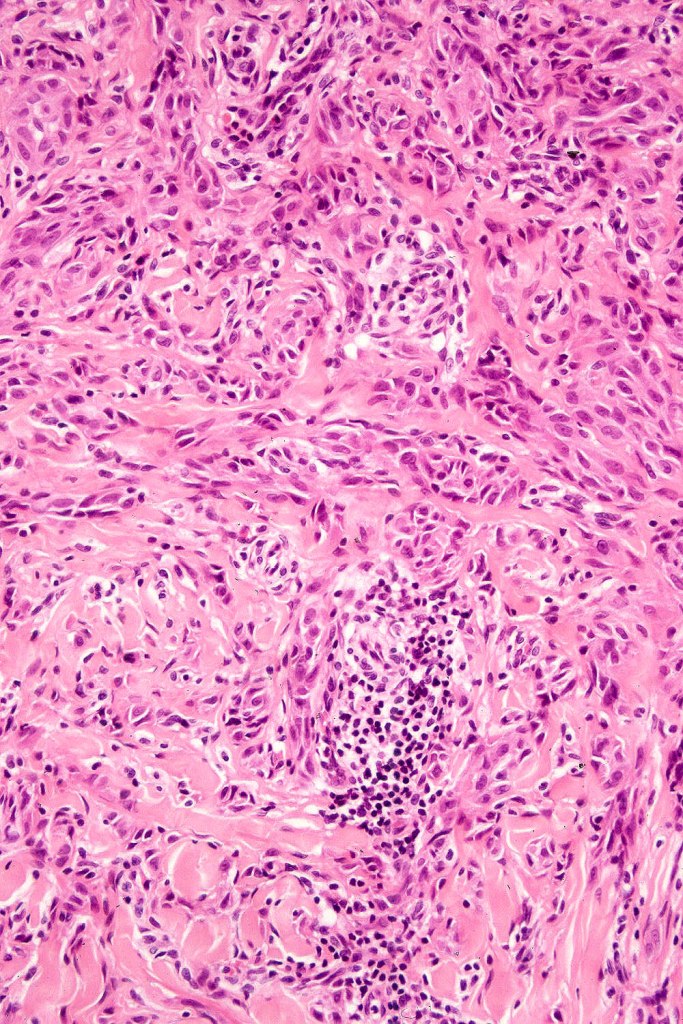

•Pleomorphism is almost invariable but affects all of the population to the same extent i.e., the cells & nuclei all look very much the same

•Spindle cells have abundant cytoplasm and vesicular nuclei with small nucleoli

•Epithelioid cell variants often show greater pleomorphism and cells can frequently appear bizarre with abundant, sometimes ground glass cytoplasm and large vesicular nuclei with prominent eosinophilic nucleoli, multinucleate cells are often seen

•Intracytoplasmic pseudoinclusions commonly present in epithelioid cells

•Kamino bodies (often multiple) are a characteristic feature

•Lymphocytic infiltration at the base of the lesion